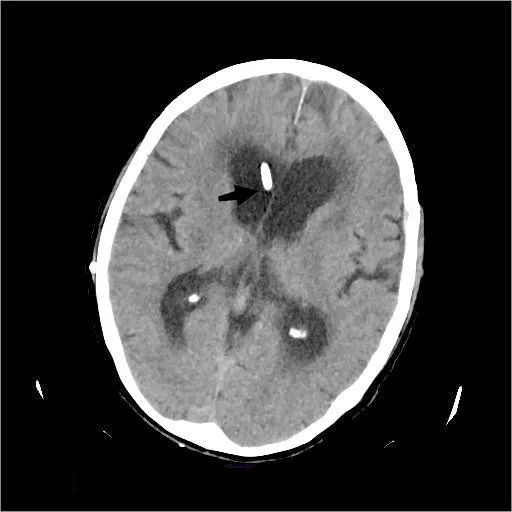

▲术后CT可见分流管脑室端

术后患者次日即精神好转,言语流利、反应敏捷,能站立扶行,神经功能改善立竿见影。